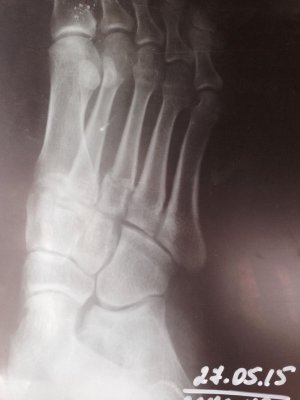

Перелом случился 2.05.2015. Неудачно споткнулась, упала и перелом. В гипсе была до 27.05.2015.на последнем приеме сделали рентген, сняли гипс и сказали рассаживаться и чем больше буду ходить, тем быстрее все заживет.